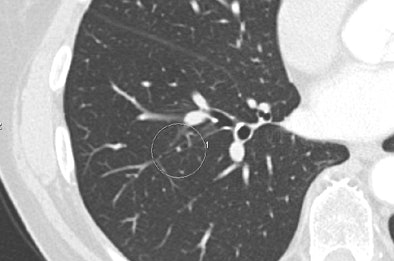

|

| Above, false-positive lesion detected by ICAD-L was actually mucus in bronchus. Below, true negative nodule detected by the reader and ICAD-L. Images courtesy of Dr. Peter Herzog. |

|